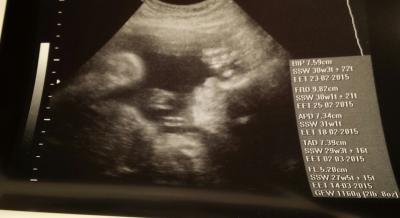

Guten Abend ihr Lieben, Sind auch zurück und bin mal wieder nur schnell abgefertigt worden wie ich finde sodass ich vom Auto aus sogar nochmal in der Praxis angerufen hab um zu Fragen wie groß die Kleine Maus nun eigentlich ist.....hmmm bescheuert. Die Schwester hat sich entschuldigt dass momentan alles drunter und drüber geht und leider manche Dinge unter den Tisch fallen...mein Eisenwert fehlt, die Wachstumskurve wird nicht markiert und irgendwie wurde echt alles vergessen....hätte ich nicht gesagt dass ich heute bitte Blut abgenommen haben möchte dann hätten die das auch wieder verpeilt Langsam nervt mich das.... Jedenfalls soll Sie 1160g wiegen und 32cm sein. Komischer Weise war ich vor 2 Wochen im KH und da war sie schon ein Kilo schwer und bei 37cm Klar sind nur Schätzwerte aber das finde ich schon arg komisch! Naja nun gut, Sie liegt in SL und war sehr agil mal wieder und von daher mache ich mir keine Sorgen. Hier noch ein kleines Bild von der süßen Motte

Bild zu Auch zurück vom letzten Screening und CTG ....Größe & Gewicht!? - Forum für März - Mamis